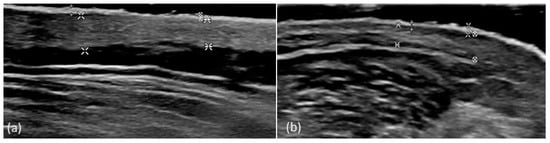

3.1. High-Frequency Ultrasound

4.1. Cutaneous Ultrasound

| Plaque epidermis thickness | 0.074 | 0.095 | 0.108 |

| Perilesional epidermis thickness | 0.054 | 0.063 | 0.073 |

| Plaque dermis thickness | 0.159 | 0.247 | 0.377 |

| Perilesional epidermis thickness | 0.139 | 0.200 | 0.275 |